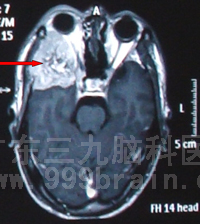

治疗前可见颅内转移癌(红色箭头处)

肿瘤空间位置示意图(箭头位置) 肿瘤三维重建示意图(箭头位置)